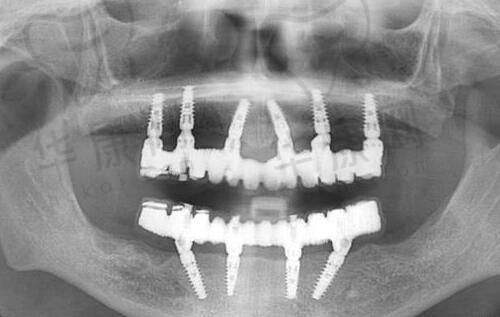

20年前的注射丰胸材料主要有玻尿酸、自体脂肪、奥美定、英吉尔法勒等。玻尿酸是常见材料,有良好的保湿和塑形成效,不过因其可吸收性,需多次注射才能达到理想状态。自体脂肪是从身体其他部位抽取脂肪细胞注入乳房,相对安心可靠,但可能要多次手术才有明显成效。而奥美定和英捷尔法勒这两种聚丙烯酰胺水凝胶材料,曾广泛用于整形美容行业。然而,自2000年初起,它们被判定为违禁药品,因为存在诸多副作用和风险,比如可能引起感染、疼痛、结节、变形等问题,甚至有增加患乳腺癌的风险。如果20年前使用了这两种材料进行注射丰胸,建议尽快联系医生或医疗机构取出。

一般情况下,注射丰胸不会导致癌变。常用的自体脂肪或玻尿酸材料,通常不会产生有害物质,不会增加癌变风险。但要是使用了奥美定材料,就存在癌变风险。尽管目前没有直接科学证据表明奥美定会导致乳腺癌,但它在体内会分解成有毒单体,影响神经系统,造成内分泌紊乱,损伤肾脏,危害生命循环系统,还被卫生组织列为可疑致癌物。所以,曾用奥美定隆胸的女性,应尽早到医院取出注射物,手术要选择正规有资质的医疗机构和经验多的医生,以保护手术安心和成效。总之,注射丰胸本身不一定会致癌,但要在合法安心的前提下进行,术后做好护理保养,有不适及时就医。

如果想取出20年前注射的隆胸材料,广州荔湾区是个不错的选择,这里拥有全息六维层离清奥技术。建议选择正规医疗机构和有经验的医生进行手术,像大型综合性医院、正规整形医院或有相关资质经验的诊所都可以。广州荔湾区在奥美定取出方面优势显著。这里有正规的医生团队,他们在奥美定取出领域理论基础深厚、实践经验多,能精细判断奥美定位置和分布,采用合适方法取出。医院还引进了精良的内窥镜设备和高清3D内镜技术,可在直视下手术,确保精细度和安心性,避开血管、神经和组织,减少创伤,加快术后修复。并且会根据患者具体情况和需求制定个性化手术方案,综合考虑奥美定大小、位置和患者身体状况等因素,让手术更精细有效。术后还提供系统护理服务,包括伤口护理、疼痛管理等,医生会根据患者情况及时调整方案,助患者尽快修复到良好状态。